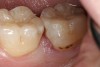

Replacement of existing restorations is responsible for 75% of all operative dentistry.15,19 The reasons for placement and replacement of restorations of direct restorative materials include: primary caries (Figure 1 and Figure 2); recurrent caries (Figure 3); poor margins (Figure 4 and Figure 5); restoration fracture (Figure 6 and Figure 7); tooth fracture (Figure 8); esthetics (Figure 9); non-carious tooth structure lost (attrition, abrasion, abfraction, erosion) (Figure 10); and pain/sensitivity.

Figure 3  Maxillary first molar with mesiobuccal tooth fracture and recurrent caries.

Figure 3